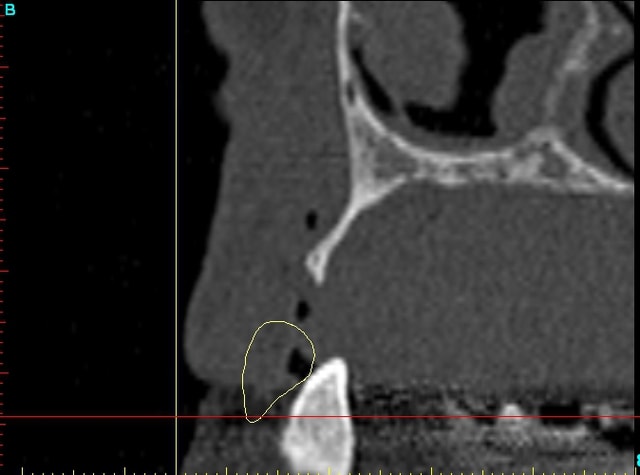

Dar12 dmdcf3 - Eugenol

Dar13 snfr77 - Eugenol

14dar tm9a6n - Eugenol

Dar14 mu6ia0 - Eugenol

15dar srylok - Eugenol

23dar fu8chl - Eugenol

Dar23 cngblb - Eugenol

24dar rfsfid - Eugenol

Dar24 scegbz - Eugenol

25dar yv2tvr - Eugenol

Dar15 gpvqe1 - Eugenol

Dar25 mrwngv - Eugenol

12dar ujxzdu - Eugenol

13dar zaa5vz - Eugenol

22dar mrs1pw - Eugenol

Darcl12.12 - Eugenol